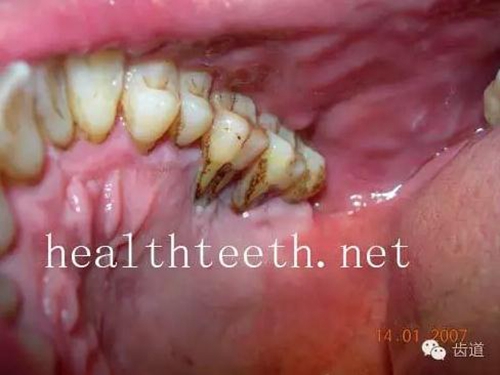

二、牙周組織病

牙周大量牙石堆積